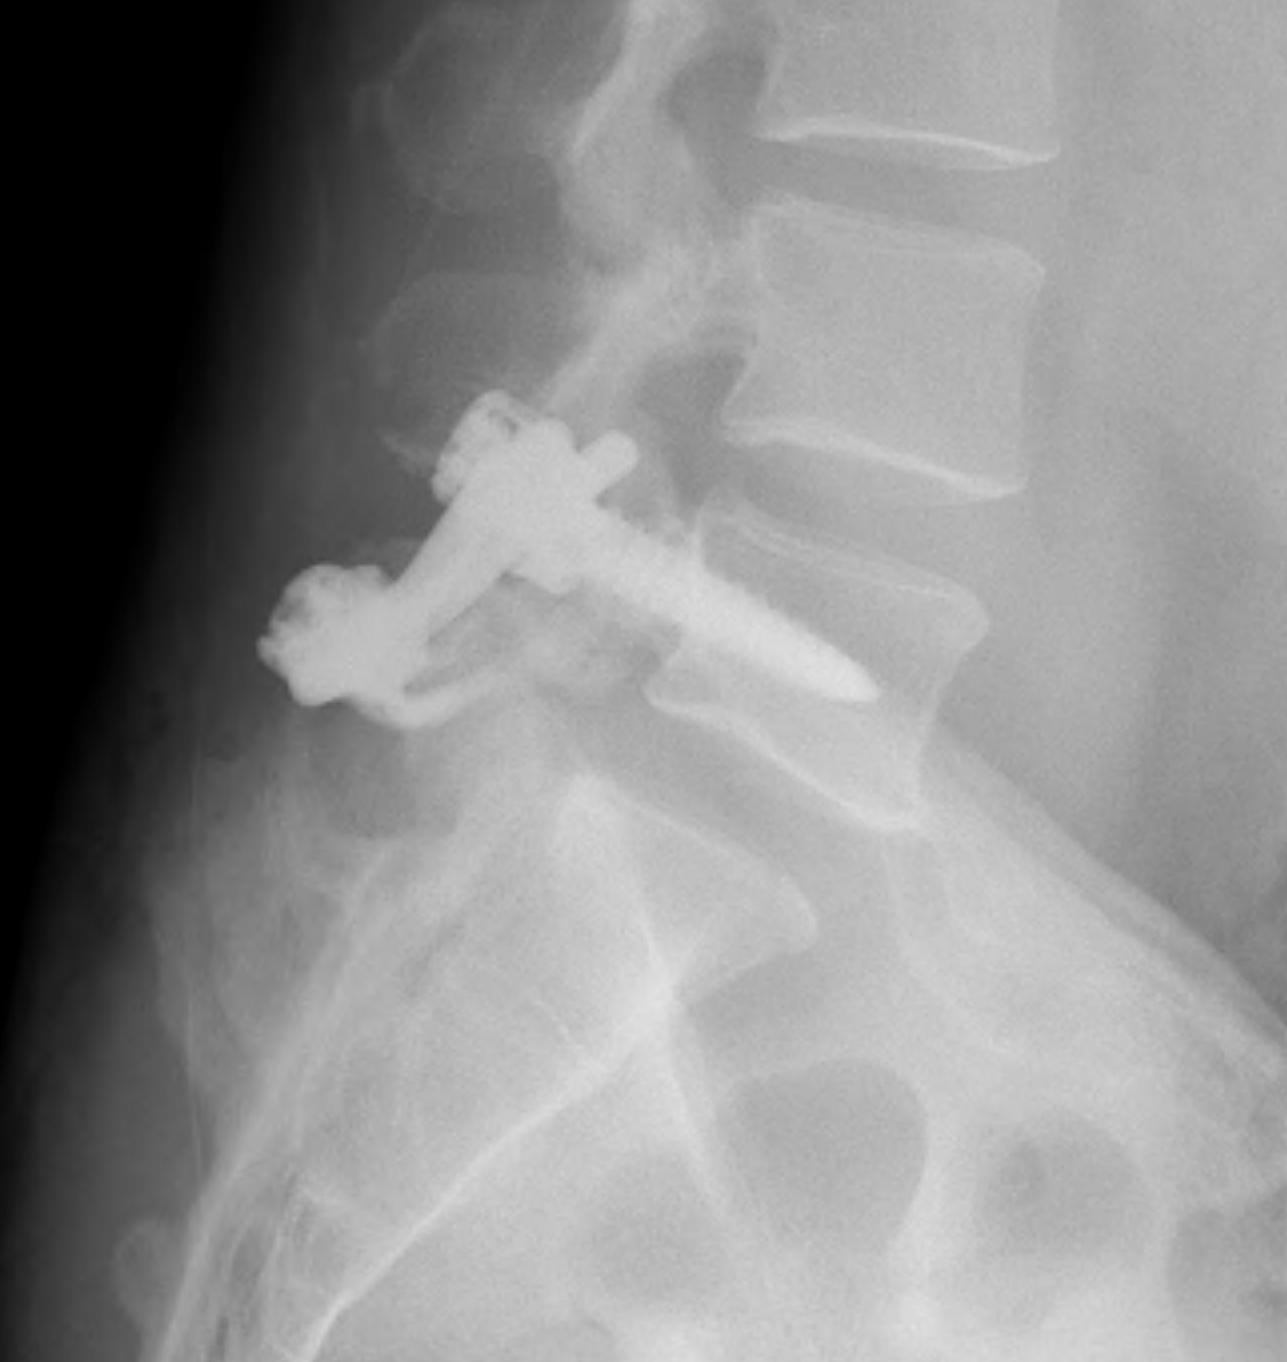

Instrumented fusion in situ without reduction

Indications

- slip grade 1 or II

- grade III or IV with no sagittal malalignment

Levels instrumentation

- L5 / S1 grade I or II

- L4 / S1 grade III or IV

Options

1. Pedicle screw instrumentation

2. PLIF / interbody cage

3. Bohlman procedure

- interbody fusion with fibula strut

- augmented with decompression and PLF

4. Transfixing L5 / sacral screw

2. Fusion

B. Instrumented / non instrumented

C. Levels

- L5/S1 if grade I or II / 50% or less

- L4/S1 if 50% for more

D. Interbody cages

- useful in long standing spondylolithesis presenting in adulthood

- degenerative disc disease

- nerve root pain from interforaminal compression

- improves nerve root space

- improves healing rate